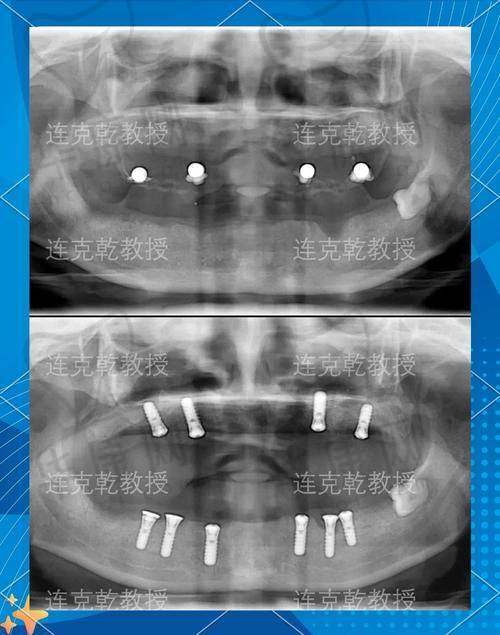

我按照网上查到的地址来到了成都医大口腔医院,它位于成都市武侯区新南路40号,交通特别方便,我坐地铁3号线到衣冠庙站,从C口出来后步行大约500米就到了。一进医院,前台的工作人员就热情地接待了我,引导我挂号、填写资料。之后,医生给我做了全方面的口腔检查,包括拍X光片、CT等,详细了解我的口腔状况,看看我的牙槽骨条件是否适合种植牙,还评估了我的身体状况是否能承受种植牙手术。检查过程中,医生特别耐心,会跟我解释每一项检查的目的和结果。

成都医大口腔医院全口种植牙之手术过程

手术前,护士给我讲解了手术的注意事项,让我放松心情,不要紧张。手术时,医生和护士配合得特别默契,会时不时问我感受如何。打麻药的时候有点疼,但可以忍受,麻药起效后就没什么感觉了。整个手术过程中,医生操作特别熟练,利用精良的技术精细地植入种植体。虽然我心里还是有点忐忑,但看到医生专精的样子,我渐渐就放心了。手术大概进行了几个小时,结束后医生详细地跟我交代了术后的护理事项。